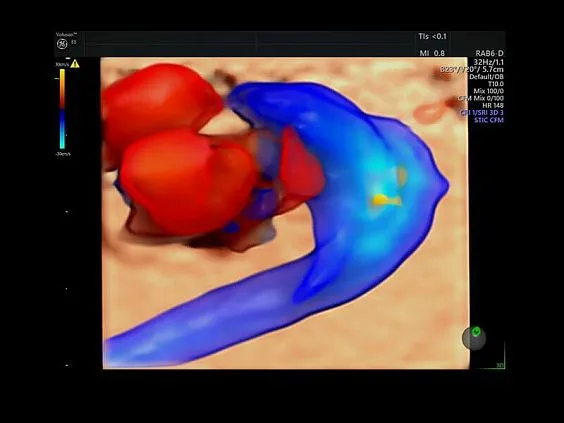

Клинические изображения

- HDlive Flow — перемещаемый источник света, совместимый с визуализацией кровотока в 3D.

- HDlive Flow Silhouette — режим «Силуэт» с выделением границ полостей сердца и сосудов, совместимый с визуализацией кровотока.

- HDlive Flow — перемещаемый источник света, совместимый с визуализацией кровотока в 3D.

- HDlive Flow Silhouette — режим «Силуэт» с выделением границ полостей сердца и сосудов, совместимый с визуализацией кровотока.

- Advanced STIC — расширенный программный пакет для исследования сердца плода в режиме 4D для объемных датчиков:

- Использование цветного, энергетического допплера, В Flow — режим STIC.

HDlive Flow и Flow Silhouette помогают детально визуализировать сосудистую сеть и анатомические особенности кровотока.